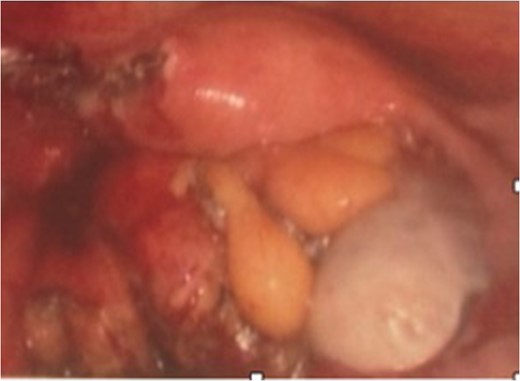

Two weeks later the patient was taken to the operating room for a hand-assisted laparoscopic colon resection and left oophorectomy. Intraoperatively, there were adhesions between the sigmoid colon and left anterolateral pelvic sidewall. Figure 3 shows the inflamed left ovary and fallopian tube adjacent to the sigmoid colon. The left ovary and a small portion of the left fallopian tube were dissected, and then resected en bloc with the sigmoid colon. Figure 4 depicts the uterus status post-resection. An end-to-end anastomosis was performed to the inraperitoneal rectum. The patient had an uncomplicated hospital course and was discharged home on post-operative Day number 2. One month later, the patient was doing well with normal bowel function, resolution of her UTI’s and resolved abdominal pain.

Pathologic exam revealed a resected portion of rectosigmoid that contained a diverticulum that had fistulized into the attached ovarian tissue, seen in Fig. 5. An adherent portion of fallopian tube was also present. The fistula tract was lined by granulation tissue with acute and chronic inflammatory cells and focal foreign body giant cells as seen in Fig. 6. The fistula extended into the ovarian stroma, causing a focal tuboovarian abscess. No other diverticula were present.

Gross photograph showing colonic diverticulum extending into pericolonic fat and forming a fistula to the underlying ovarian tissue.